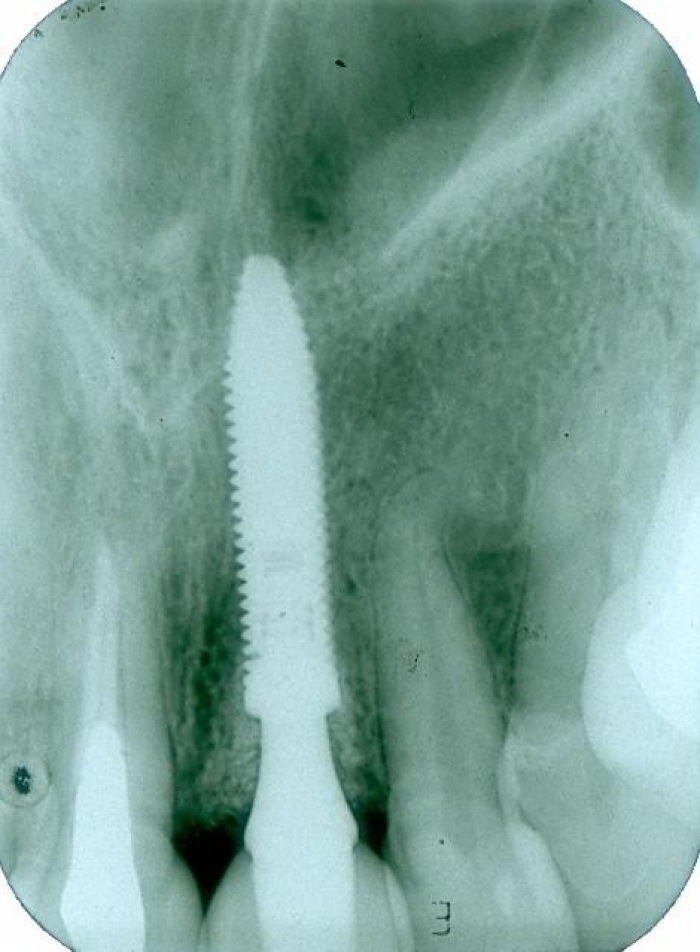

Raio X após instalação de um implante inferior